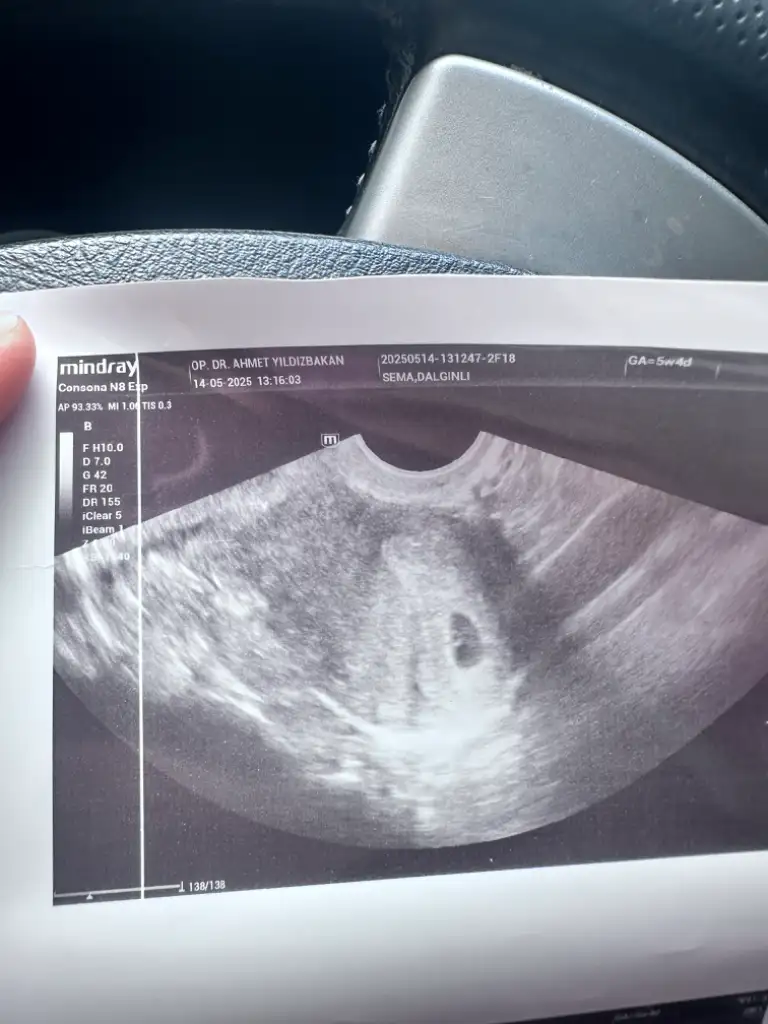

Kızlar selam keseme bakar mısınız normal mi 5+2 bugün

5+4 haftalıksın cnm ultrasyon kâğıdın öyle dior